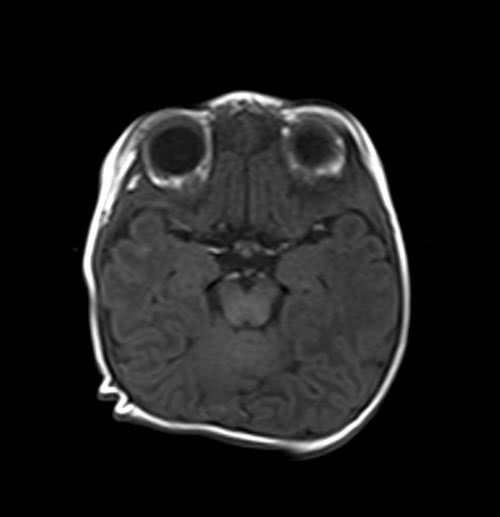

MRI pediatric brain axial T1 images